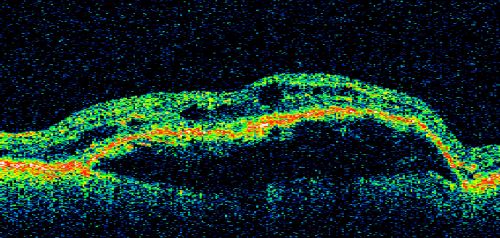

Wet AMD - PED with exudate 20/400 87 Year old

87-year-old woman has wet age-related macular degeneration in the left eye. Vision OD is 20/25, OS is 20/400